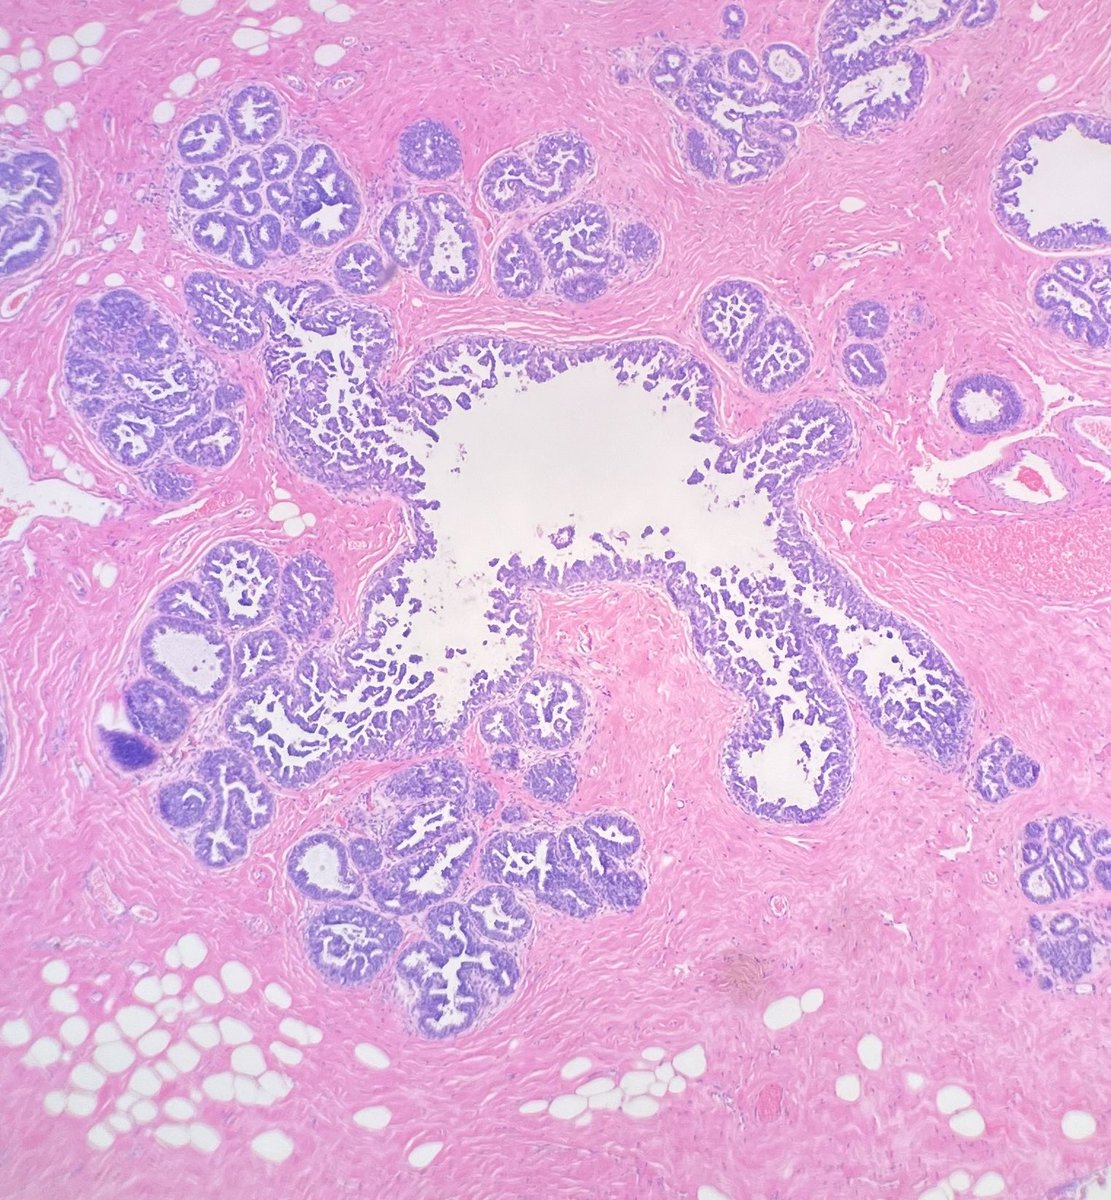

Micropapillary ductal carcinoma in situ involving a camel 🐫 Accepting contributions for my future Atlas of Emojis in Pathology!! Reply with yours!